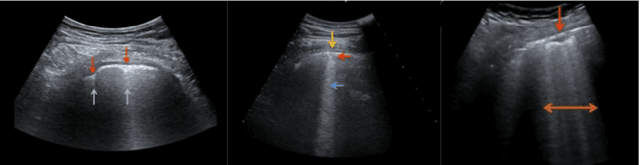

Abstract:The Coronavirus Disease 2019 (COVID-19) pandemic has impacted many aspects of life globally, and a critical factor in mitigating its effects is screening individuals for infections, thereby allowing for both proper treatment for those individuals as well as action to be taken to prevent further spread of the virus. Point-of-care ultrasound (POCUS) imaging has been proposed as a screening tool as it is a much cheaper and easier to apply imaging modality than others that are traditionally used for pulmonary examinations, namely chest x-ray and computed tomography. Given the scarcity of expert radiologists for interpreting POCUS examinations in many highly affected regions around the world, low-cost deep learning-driven clinical decision support solutions can have a large impact during the on-going pandemic. Motivated by this, we introduce COVID-Net US, a highly efficient, self-attention deep convolutional neural network design tailored for COVID-19 screening from lung POCUS images. Experimental results show that the proposed COVID-Net US can achieve an AUC of over 0.98 while achieving 353X lower architectural complexity, 62X lower computational complexity, and 14.3X faster inference times on a Raspberry Pi. Clinical validation was also conducted, where select cases were reviewed and reported on by a practicing clinician (20 years of clinical practice) specializing in intensive care (ICU) and 15 years of expertise in POCUS interpretation. To advocate affordable healthcare and artificial intelligence for resource-constrained environments, we have made COVID-Net US open source and publicly available as part of the COVID-Net open source initiative.

Abstract:The COVID-19 pandemic continues to have a devastating effect on the health and well-being of the global population. Apart from the global health crises, the pandemic has also caused significant economic and financial difficulties and socio-physiological implications. Effective screening, triage, treatment planning, and prognostication of outcome plays a key role in controlling the pandemic. Recent studies have highlighted the role of point-of-care ultrasound imaging for COVID-19 screening and prognosis, particularly given that it is non-invasive, globally available, and easy-to-sanitize. Motivated by these attributes and the promise of artificial intelligence tools to aid clinicians, we introduce COVIDx-US, an open-access benchmark dataset of COVID-19 related ultrasound imaging data that is the largest of its kind. The COVIDx-US dataset was curated from multiple sources and consists of 93 lung ultrasound videos and 10,774 processed images of patients infected with SARS-CoV-2 pneumonia, non-SARS-CoV-2 pneumonia, as well as healthy control cases. The dataset was systematically processed and validated specifically for the purpose of building and evaluating artificial intelligence algorithms and models.